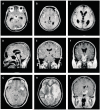

Findings: 83 scans were done for 43 patients: 19 given placebo, 24 given dexamethasone. Basal meningeal enhancement (82%) and hydrocephalus (77%) were the most common presenting findings. Fewer patients had hydrocephalus after 60 days of treatment with dexamethasone than after placebo treatment (p=0.217). Tuberculomas developed in 74% of patients during treatment and in equal proportions in the treatment groups; they were associated with long-term fever, but not relapse or poor clinical outcome. The basal ganglia were the most common site of infarction; the proportion with infarction after 60 days was halved in the dexamethasone group (27%vs 58%, p=0.130).

Interpretation: Dexamethasone may affect outcome from tuberculous meningitis by reducing hydrocephalus and preventing infarction. The effect may have been under-estimated because the most severe patients could not be scanned.